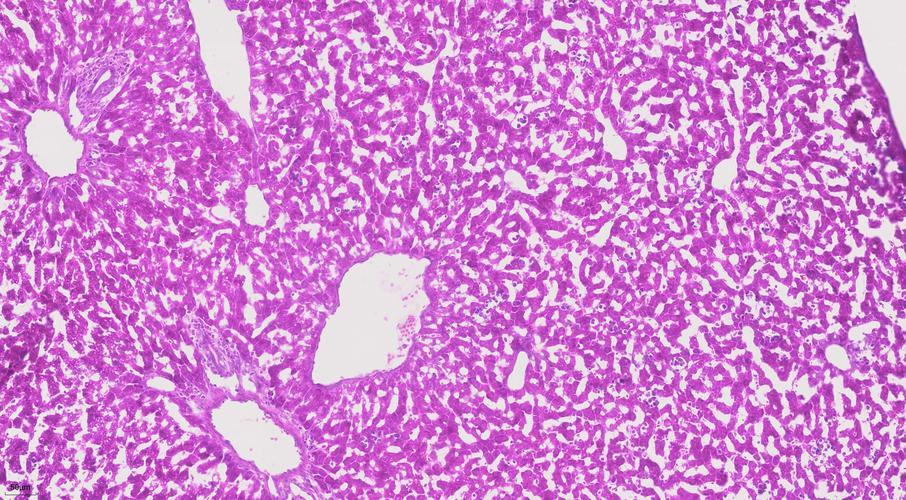

经过一系列的固定、脱水、石蜡包埋处理后,患者的组织被精心切成4微米的薄片。随后,采用苏木精-伊红(H&E)染色技术,使得细胞核呈现出鲜明的蓝色,而胞质则被染成粉色。在光学显微镜下,这些染色后的细胞首次揭示了其形态上的病理改变。病理医生能够直观地观察到细胞的形态、大小、排列方式以及细胞核的独特特征。